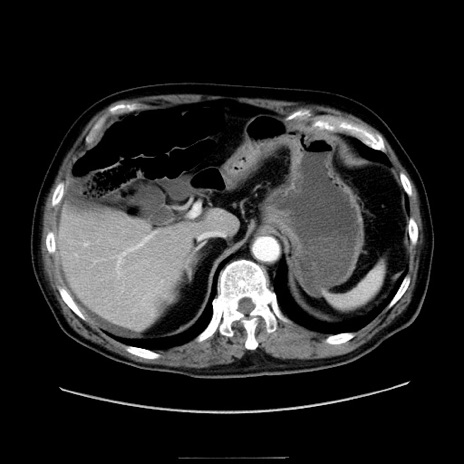

症例30(横断像)

【症例】80歳代男性

【主訴】臍周囲痛

【現病歴】約6時間前から臍下部痛が出現。次第に腹部膨隆・背部痛も生じてきたため来院。背部痛の場所は変化しない。

【身体所見】意識清明、BT 36.3℃、BP  131/87mmHg、P 87bpm、SpO2 100%(RA)、臍周囲自発痛・圧痛あり、反跳痛なし、自発痛部位に一致して板状硬あり、腹部膨隆、腸雑音減弱、CVA tenderness両側陰性。